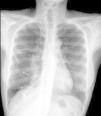

Objetivo. Mostrar la forma de presentación y los hallazgos radiológicos del neumotórax catamenial. Material y método. Se revisaron las pruebas de imagen (radiografía simple, tomografía computarizada [TC] y resonancia magnética [RM]) de 6 mujeres de entre 28 y 44 años que presentaron neumotórax recurrentes asociados a la menstruación. A todas se les realizó cirugía por videotoracoscopia (VTS) y en tres de ellas fue necesaria la realización de una toracotomía debido a la recurrencia del neumotórax. Resultados. En tres casos se realizó TC, encontrando nódulos pleurales en dos casos, uno de ellos confirmado en la RM. Histológicamente se demostró endometriosis pleural en un único caso. Se identificaron agujeros diafragmáticos y bullas en 5 de las 6 pacientes. Discusión. Los síntomas más frecuentes del neumotórax catamenial son el dolor torácico, la disnea y la hemoptisis. La localización más frecuente es el lado derecho (90%). Los hallazgos radiológicos son neumotórax, hemotórax o hidroneumotórax. La TC y la RM pueden ayudar en la identificación de lesiones pleurales no visibles en la radiografía simple que suponen un hallazgo muy frecuente en la cirugía. Conclusión. El diagnóstico de neumotórax catamenial debe sospecharse en mujeres en edad fértil con historia de neumotórax recidivantes coincidentes con la menstruación. La TC y la RM pueden ayudar a identificar lesiones sospechosas de endometriosis.

Material and methods. We reviewed the imaging tests (plain-film radiography, computed tomography [CT], magnetic resonance [MR]) performed in six women aged between 28 and 44 years with recurrent pneumothorax associated to menstruation. All patients underwent videothoracoscopic surgery and thoracotomy was necessary in three due to the recurrence of the pneumothorax. Results. CT was performed in three cases and found pleural nodules in two; one of these was confirmed at MR. Pleural endometriosis was only demonstrated at histological examination in one case. Diaphragmatic blebs and bullae were found in five of the six patients. Discussion. The most common symptoms of catamenial pneumothorax are chest pain, dyspnea, and hemoptysis. The right side is affected in 90% of cases. The radiological findings are pneumothorax, hemothorax, or hydropneumothorax. CT and MR can help to identify the pleural lesions that are not visible on plain-film radiographs and are a very common finding at surgery. Conclusion. The diagnosis of catamenial pneumothorax should be suspected in fertile-aged women with a history of recurrent pneumothorax coinciding with menstruation. CT and MR can help to identify lesions suspicious of endometriosis.